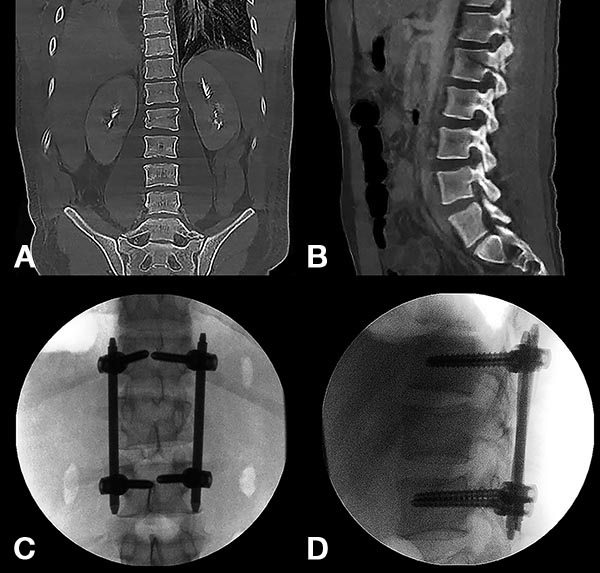

Figura 4:

Caso 8. Hombre de 52 años, accidente vehicular de alta energía cinética. Fractura cerrada de antebrazo, síndrome de distrés respiratorio, hemotórax bilateral, hematocrito en descenso. Se diagnostico una fractura A4 de T8 con mínimo compromiso del canal espinal, posición en cifosis y hemotórax bilateral a predominio izquierdo.

Figura 5:

Caso 8. Se realizó una estabilización percutánea T6-T10. El paciente retornó a UTI, para estabilizar su cuadro respiratorio y hemodinámico.

Figura 6:

Caso 8. A la semana de la primer cirugía el paciente se encontraba en condiciones y se realizó la corpectomía por via lateral MIS.

Figura 7:

Caso 8. Control postoperatorio alejado del paciente con un buen callo de fusión, sin pérdida de corrección.